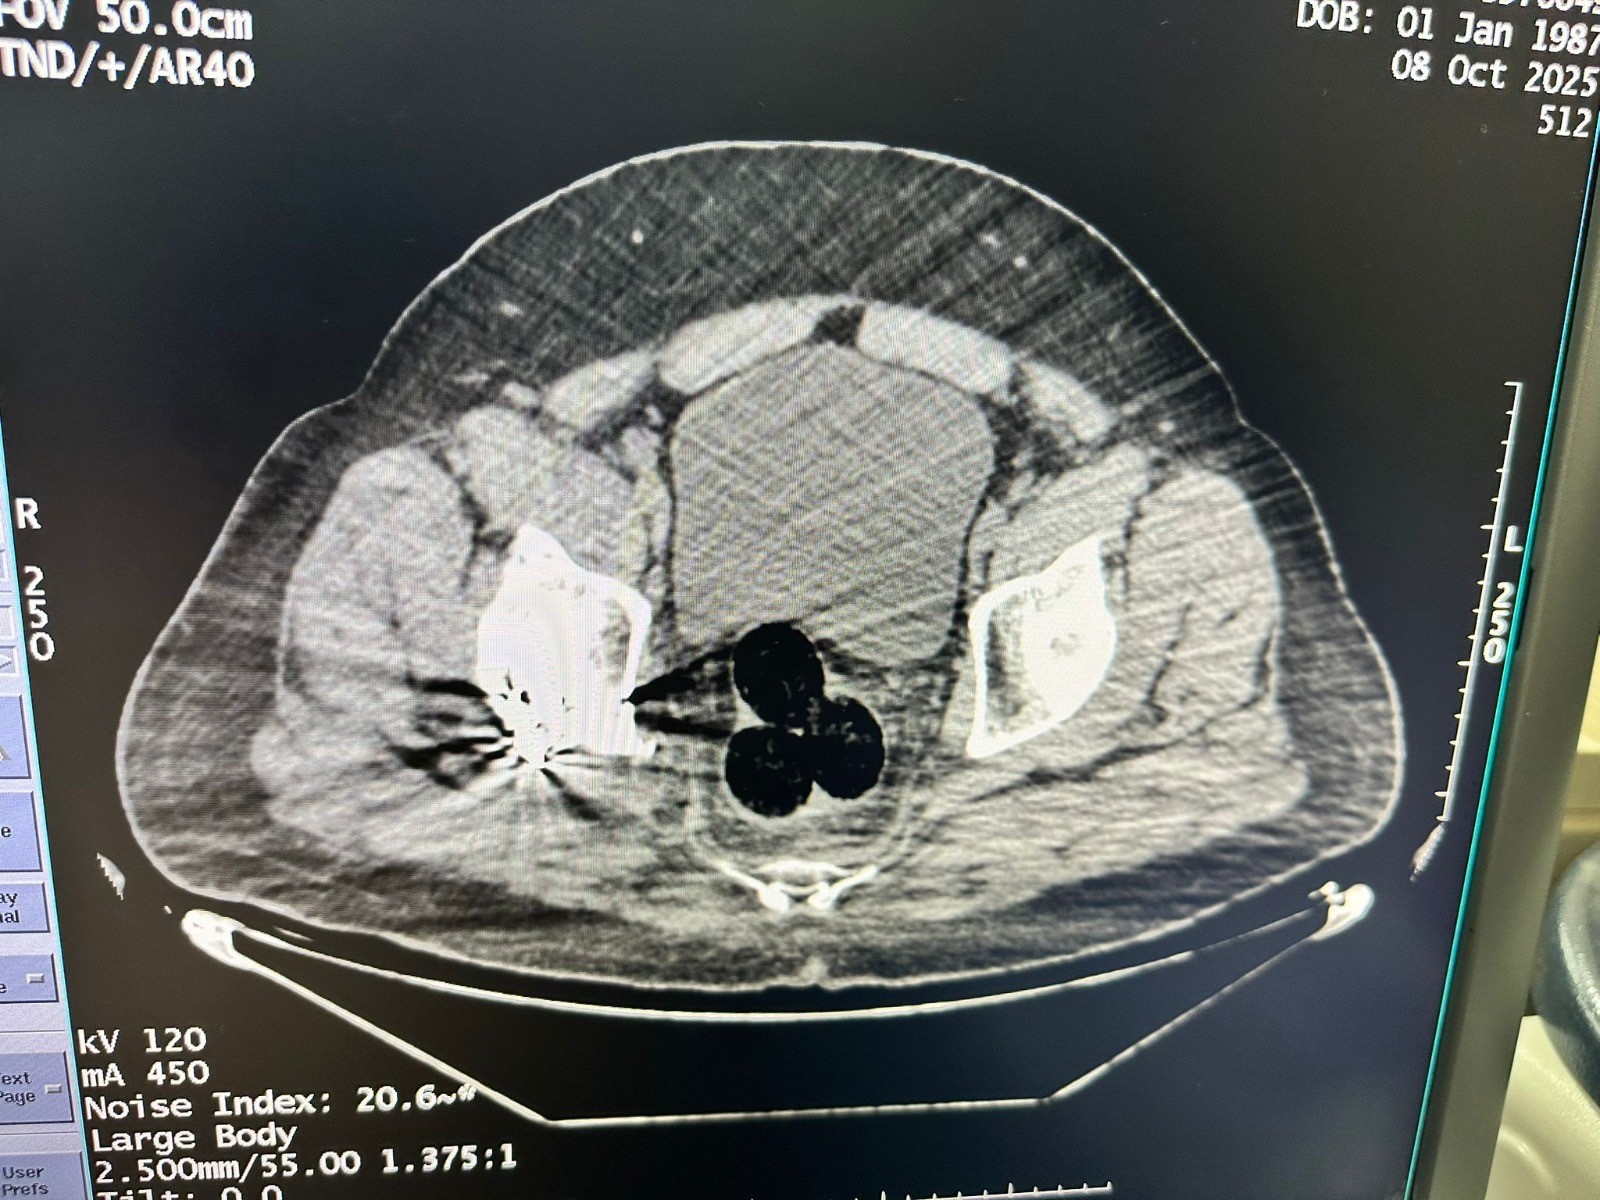

Yapılan radyolojik muayenede şüphelinin makat bölgesinde üç parça halinde yabancı cisim tespit edildi. Cerrahi müdahale sonucu çıkarılan paketlerde toplam 130 gram metamfetamin bulundu.